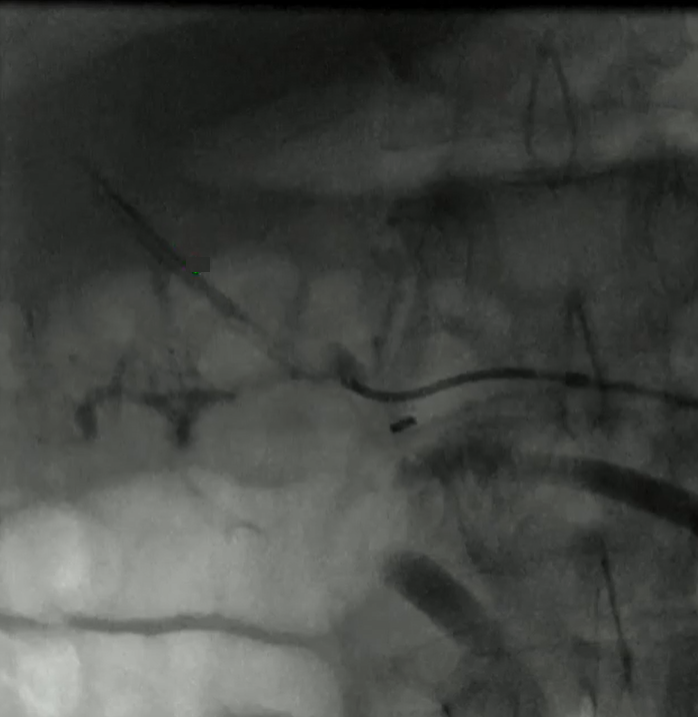

该程序包含以下步骤: 经脾脏入路:在超声引导下,刺穿脾静脉内的一个实质内分支。 在通过脾静脉造影确认了静脉通路后,导管和导丝被推进,以穿过脾静脉并抵达血栓化的门静脉。在门静脉/右门静脉分支处放置圈套器,为TIPS穿刺精准定位。TIPS穿刺圈套器,并穿过圈套器完成TIPS

步骤: 鉴于慢性血栓形成的复杂性: 一种经脾脏途径的门静脉再通术(PVR)。 随后是经颈静脉肝内门体分流术 。